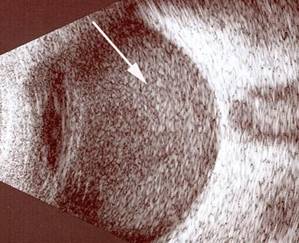

Resim 3: Normal göz ultrasonografisi görüntüsü. Vitreus siyah refle ( beyaz ok), retina beyaz refle ( siyah ok) vermektedir.